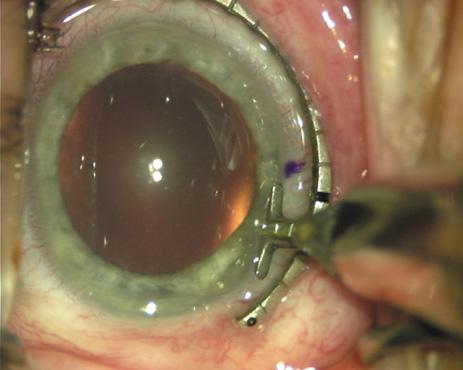

Case 3 is a 48-year-old bilateral hyperope who presented for a refractive surgical consultation. The refraction in his left eye was found to be +3.25 +1.75 × 85. Keratometry was somewhat flat but confirmed WTR cylinder as did corneal topography. Based upon the patient's age, refraction, and somewhat shallow anterior chambers, the decision was made to proceed with a refractive lens exchange. The NAPA nomogram called for LRIs of 55 to 60 degrees with intraoperative pachymetry. Intraoperative keratoscopy confirmed the steep 85-degree meridian (Figs. 2029).

Fig. 20. Keratoscopy, after lifting of the speculum to relieve induced pressure and distortion of the corneal mires, confirms the steep axis of 85 degrees.

Fig. 21. The broad hash marks of the fixation ring are centered just off of the 6:00 limbal orientation mark, over the 85 degree meridian in this left eye. The two cut RK marker is positioned at one extent of the LRI, just under 30 degrees from the central steep meridian and the cornea is marked.

Fig. 22. A second mark is made delineating the opposite extent for a total arc length of just under 60 degrees.